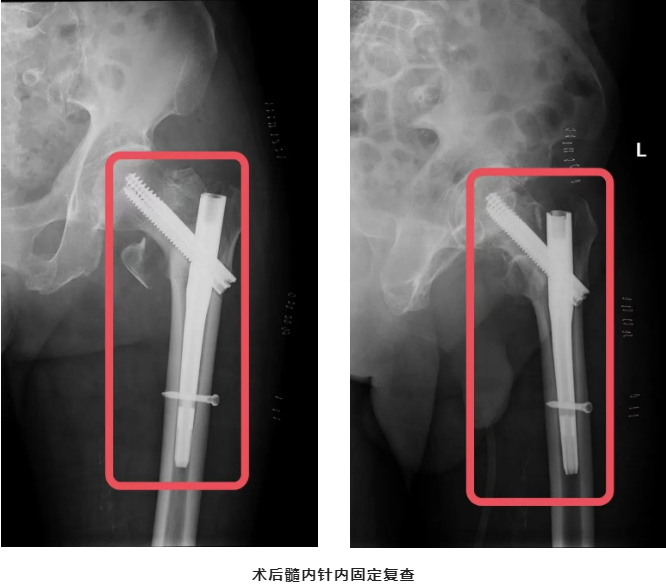

何时手术是最佳时机?肯定是越快越好!与时间赛跑,抓住48小时内的黄金期,我们骨科医护一起为老人争取。9月2日,手术如期进行,我们选择了最微创的“骨折闭合复位髓内针内固定术”,尽量减少手术的副损伤。手术9点30分开台,10点30分结束,短短1个小时时间,手术完成,张爷爷生命体征平稳,参加手术人员悬着的心终于落地。

张爷爷返回病房后,在骨科谢小明护士长带领的护士团队精心呵护下,3日后可以下床行走了,张爷爷和家属露出久违的笑容,这笑容是这那么灿烂,那么的美,同时这笑容不也是对所有参与张爷爷治疗的医护团队的肯定和感谢吗?